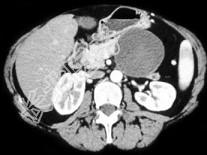

- 单项选择题如图所示,该病的鉴别诊断包括以下所有的, 除哪项以外 ( )

A、腺癌

B、Hamoudi瘤

C、囊腺瘤

D、胰腺导管内乳头状黏液性肿瘤

E、胰癌